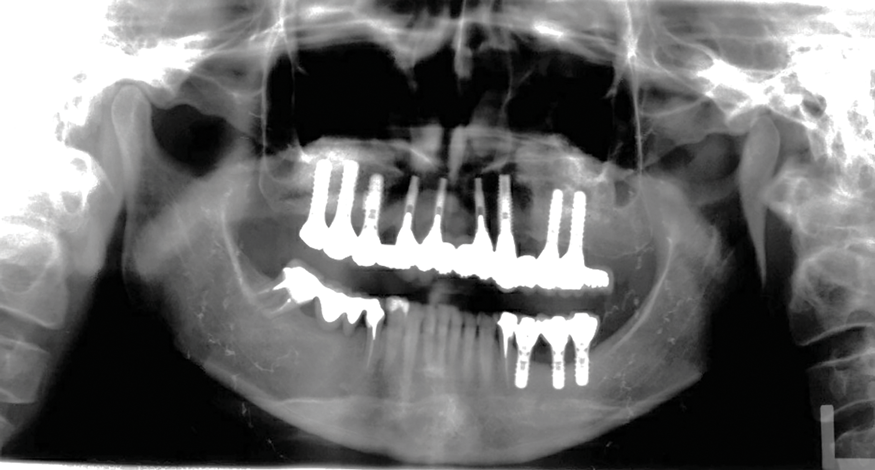

Fig 18. Panoramic radiograph at 20-year follow-up.

Figure 18

In 2020, the patient presented to the NYUCD Periodontology and Implant Dentistry Clinic. A clinical examination and radiographic evaluation showed that the patient's maxillary arch still exhibited good peri-implant soft-tissue health and stable marginal bone level with slight bone loss on implants Nos. 2, 6, 8, and 11 (Figure 18 through Figure 20). The maxillary prosthesis showed adequate stability with a slight chipped suprastructure on the porcelain on the right side. The patient was advised to substitute the implant-supported, screw-retained hybrid acrylic complete denture in the maxilla with a fixed, implant-supported, screw-retained prosthesis, which she declined due to financial considerations.